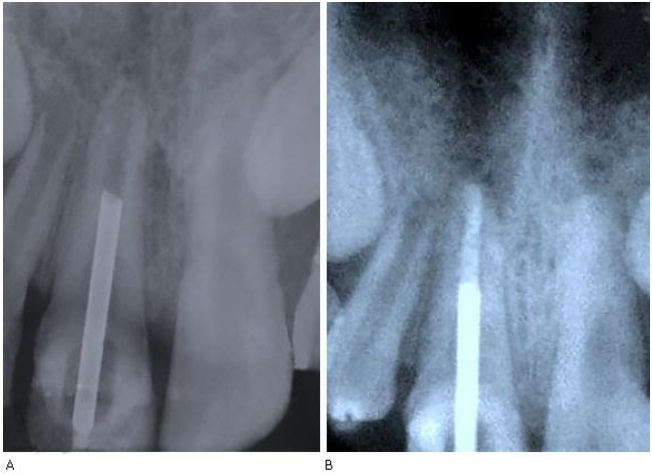

1. Se observa formación de tejido radiopaco en la región del periápice consistente con maduración apical fisiológica (Fig. 3a).

A) En la comprobación cínica radiografía de la maduración apical

11. Radiografía de comprobación (Fig. 3b).